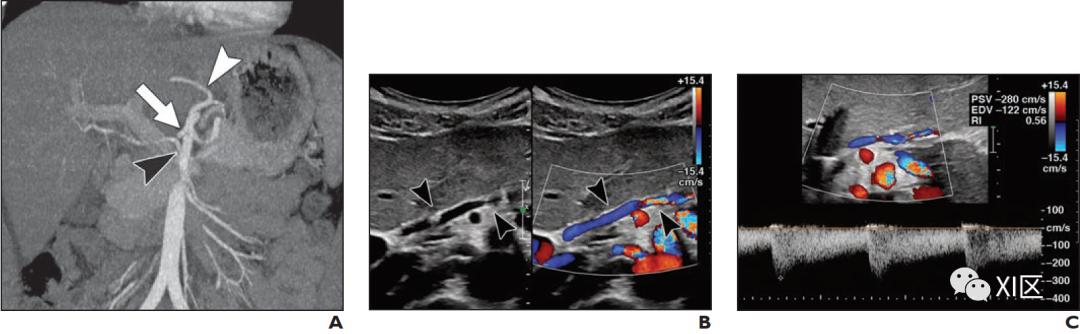

在活动性动脉-腹腔出血的CTA中,可以看到血管损伤部位的造影剂外渗病灶(图7)。延迟成像有助于区分外渗和假性动脉瘤(假性动脉瘤是一种保留圆形形态的壁内出血)之间的区别。如果没有观察到活动性外渗,CTA仍然可以通过腹腔内血肿、肿块或血管异常的位置提示出血源。CTA可以以低至0.3 ml/min的速率检测活动性出血,而在常规血管造影中为0.5 ml/min,在胃肠道出血闪烁显像中为0.1 ml/min。

术前和术后评估

术前腹部CT经常被用来确定解剖结构和帮助制定手术计划。动脉期CTA可用于辅助切除血管肿块或确定术前栓塞的可行性。此外,术前动脉期成像通常在肝移植或肝切除前用于检测异常或副肝动脉和其他血管变异(图8)。随后的门静脉期成像确定肝段解剖和切除的分期,可以除外移植前门静脉或肝静脉血栓形成。术前CTA也可用于肾移植术前有腹膜透析或血管闭塞史的小儿患者,或主动脉和下腔静脉在超声上未完全评估时。尽管灰阶和多普勒超声是移植后评估的主要成像方式,但在怀疑动脉血栓形成、狭窄或动脉瘤的情况下,CTA可作为解决问题或确认的方式(图8)。